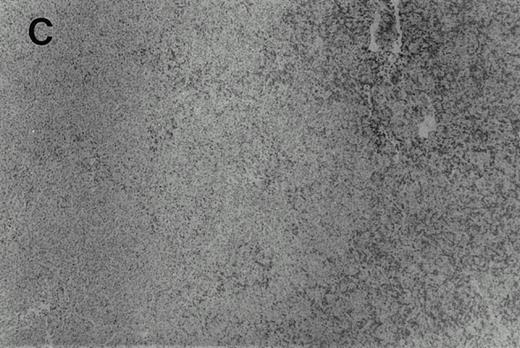

Immunohistochemistry of CD3 in case 1: (A) low (40×), (B) high (400×). CD3+ T cells are associated with clusters of H-RS cells, often forming a ring around the H-RS cells. Inset shows CD30+ H-RS cells. Immunohistochemistry of MB2 in case 2: (C) low (40×), (D) high (400×). MB2+ CLL cells are present around a nodule of HD. H-RS cells are admixed with T cells and histiocytes and only scattered MB2+ small lymphocytes are present.

The results of the immunohistochemical studies are shown in Table1 and Fig 2.The CLL cells were reactive with B-cell markers in all three cases, and also expressed CD43 in cases 2 and 3, as is commonly observed in B-CLL.23 The H-RS cells expressed CD15 and CD30 in all three cases. In case 1, a small subset of the H-RS cells also expressed CD20. The small lymphocytes forming the inflammatory background of the HD component in cases 2 and 3 were mostly T cells. Scattered B lymphocytes were also present, more prominently in case 2 where the Hodgkin's foci were less sharply demarcated from the CLL areas as compared with case 3. In case 1, although the typical cellular background of HD was absent, most of the small lymphocytes associated with the H-RS cell areas were T cells which often formed a ring around the H-RS cells.